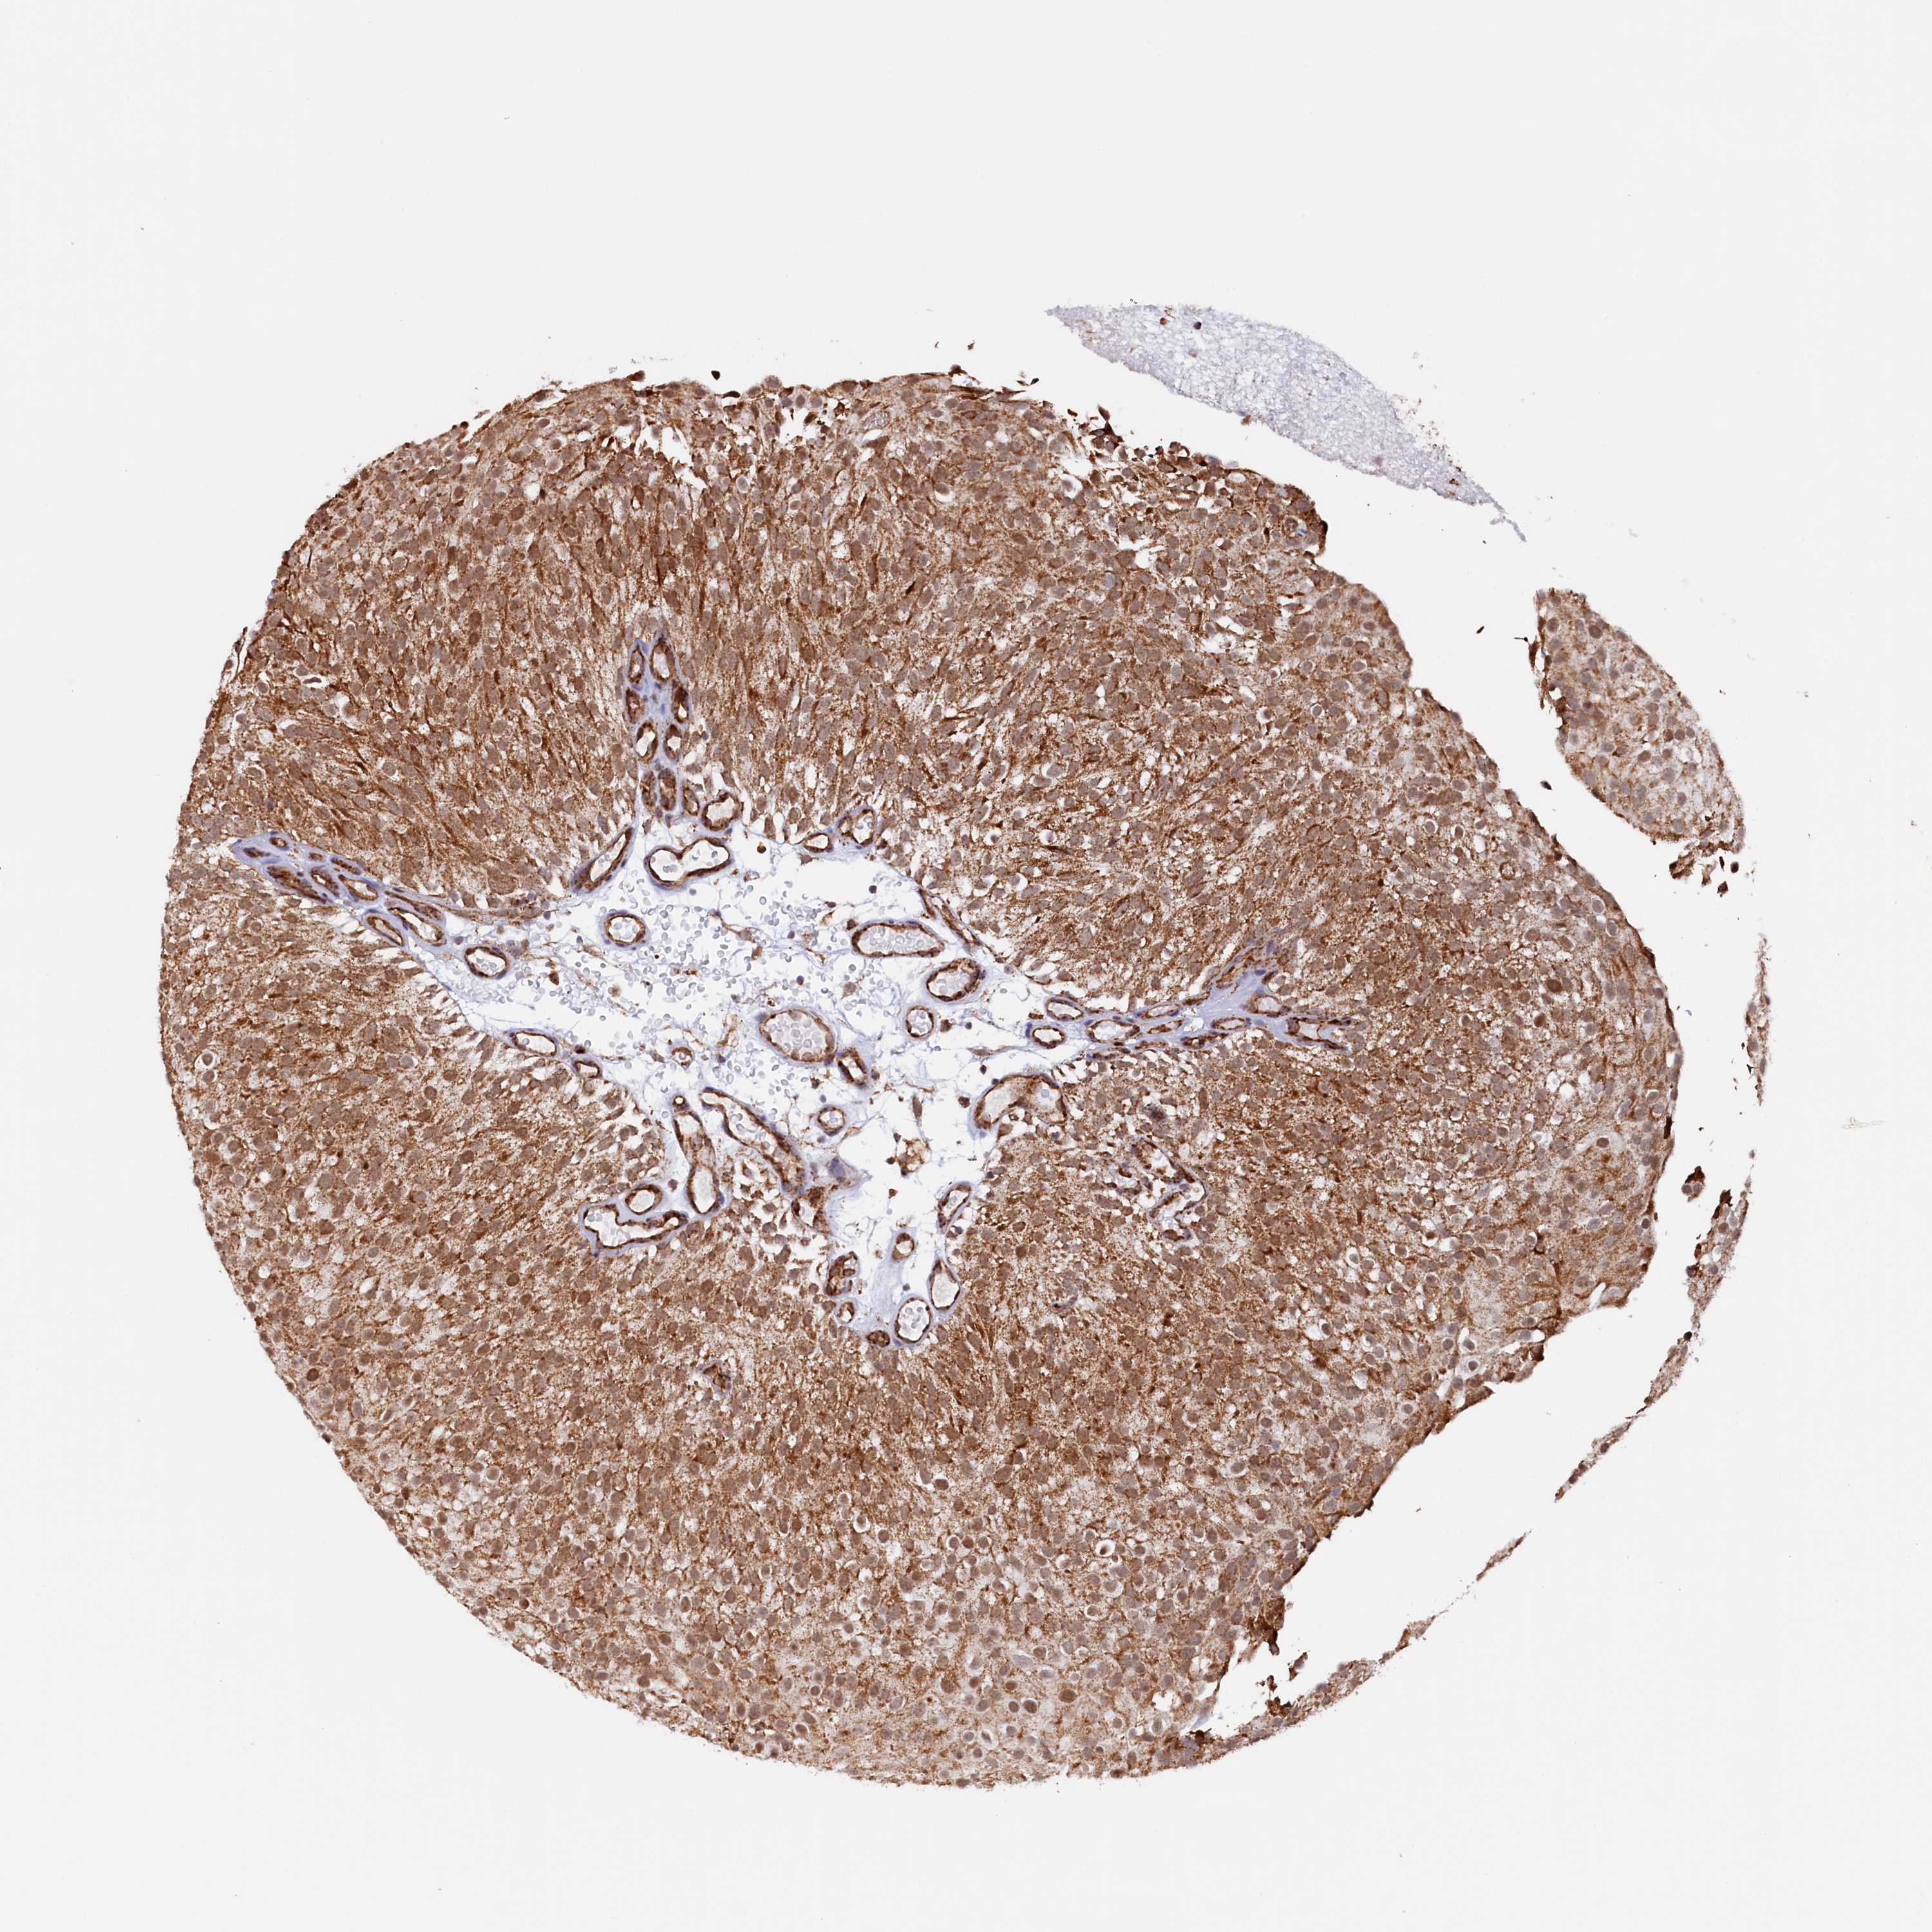

UROTHELIAL CANCER - Protein expressioni

A mouse-over function shows sample information and annotation data. Click on an image to view it in a full screen mode. Samples can be filtered based on level of antibody staining by selecting one or several of the following categories: high, medium, low and not detected. The assay and annotation is described here.

Note that samples used for immunohistochemistry by the Human Protein Atlas do not correspond to samples in the TCGA dataset.

Antibody stainingi

Antibody staining in the annotated cell types in the current human tissue is reported as not detected, low, medium, or high, based on conventional immunohistochemistry profiling in selected tissues. This score is based on the combination of the staining intensity and fraction of stained cells.

Each image is clickable and will lead to virtual microscopy that enables deeper exploration of all samples and also displays staining intensity scores, fraction scores and subcellular localization as well as patient and tissue information for each sample.

Antibody HPA041012

Staining

High

Medium

Low

Not detected

Intensity

Strong

Moderate

Weak

Negative

Quantity

>75%

75%-25%

<25%

None

Location

Nuclear

Cytoplasmic/membranous

Cytoplasmic/membranous,nuclear

Urothelial carcinoma, High grade

Urothelial carcinoma, Low grade